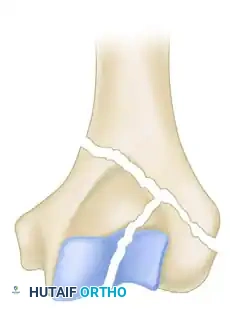

While the AO/OTA classification system is exhaustive (defining 61 types across A, B, and C categories), the Jupiter and Mehne classification, as well as the Mehne and Matta bicolumnar descriptions, offer superior utility for preoperative templating. Mehne and Matta categorize complex bicolumnar fractures based on their geometric configuration:

Mehne and Matta Medial Lambda configuration.